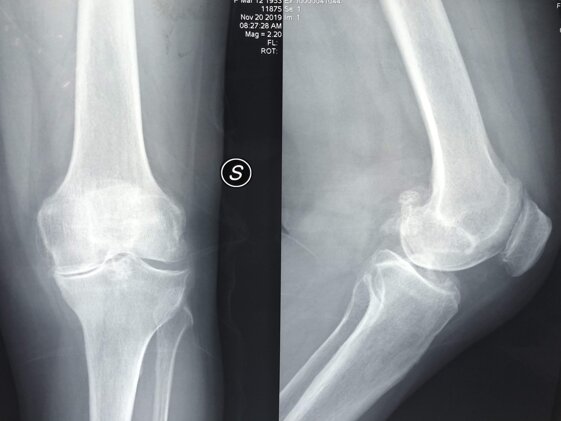

A sinistra radiografia pre-operatoria in AP e a destra radiografia post-operatoria in AP di intervento chirurgico di artroprotesi cementata di ginocchio sinistro con conservazione LCP (CR). La pz 5 anni prima era stata sottoposta ad una meniscectomia in artroscopia per una lesione del menisco mediale e durante l’intervento era stata evidenziata una condropatia avanzata femoro-rotulea e del compartimento mediale. Nel corso degli anni successivi erano stati effettuati trattamenti infiltrativi con vari tipi di acido ialuronico e con PRP (medicina rigenerativa) traendo parziali e temporanei benefici

A sinistra radiografie pre-operatorie in AP e LL e a destra radiografia post-operatoria in AP di intervento chirurgico di artroprotesi cementata ginocchio sinistro a conservazione del LCP (CR). In questa pz ho utilizzato una protesi chiamata Persona proprio perché altamente anatomica, cioè molto rispettosa dell’anatomia del ginocchio del singolo paziente

A sinistra radiografie pre-operatorie il AP e LL che evidenziano una grave gonartrosi diffusa con presenza di osteofiti periarticolari e deformità associata (ginocchio varo).

A destra radiografia post-operatoria in AP di intervento chirurgico di artroprotesi di ginocchio cementata, unico trattamento possibile con pz che presentava dolore continuo e zoppia. Ho utilizzato una protesi con risparmio del legamento crociato posteriore (CR) chiamata Persona proprio perché altamente anatomica, cioè molto rispettosa dell’anatomia del ginocchio del singolo paziente

A destra radiografia post-operatoria in AP e LL di intervento chirurgico di artroprotesi di ginocchio cementata, unico trattamento possibile con pz che presentava dolore continuo e zoppia. Ho utilizzato una protesi con risparmio del legamento crociato posteriore (CR) chiamata Persona proprio perché altamente anatomica, cioè molto rispettosa dell’anatomia del ginocchio del singolo paziente. La paziente presentava un sovrappeso per cui ho optato per una componente protesica tibiale con un fittone più lungo proprio per avere più resistenza